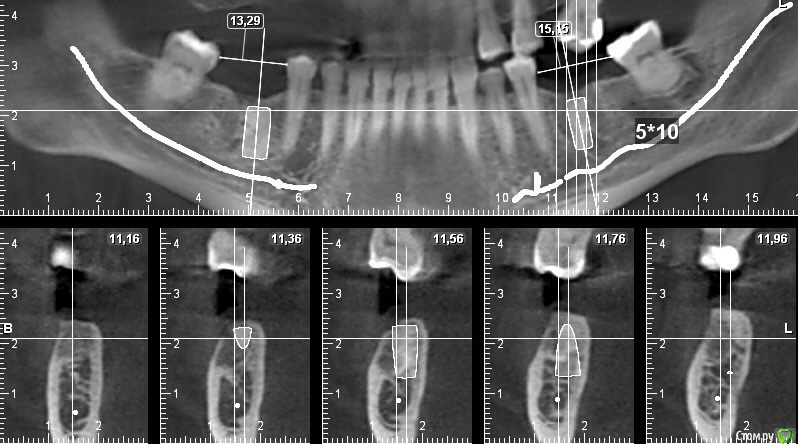

stommm Опубликовано 9 декабря, 2014 Поделиться Опубликовано 9 декабря, 2014 Я себе вот такие делаюРазметки от Вас (как в первом посте) хоть и смотрю, но практически не использую для планирования. Может дело привычки... 1 Ссылка на комментарий

ILGAMSA Опубликовано 10 декабря, 2014 Поделиться Опубликовано 10 декабря, 2014 Увидев на КТ такую кость, начинаю бояться, что пациент отпишется... 8 Ссылка на комментарий